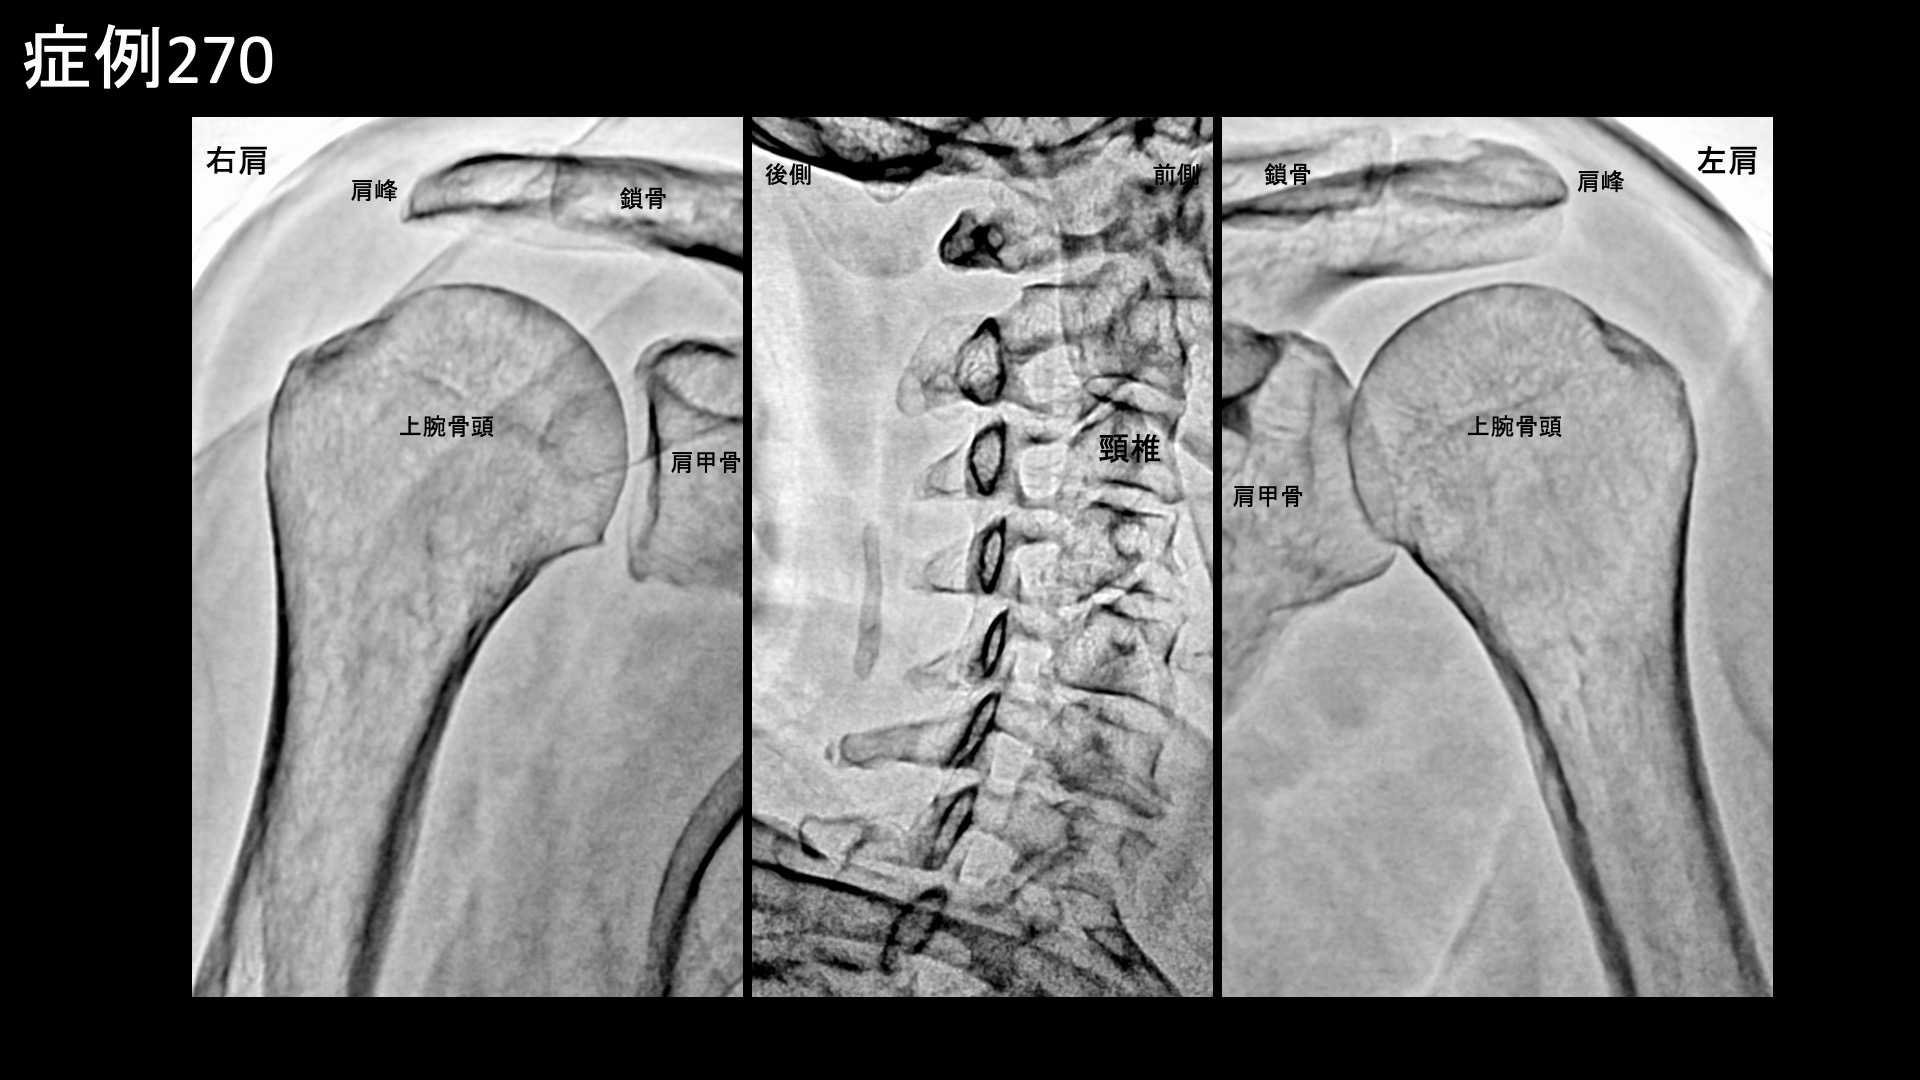

肩:肩こり・四十肩・五十肩 【50代:女性】両腕が使えず夜も眠れず、生活を一変させたまさかの両側五十肩に対するモヤモヤ血管治療(五十肩、凍結肩、肩関節周囲炎) 2026.03.13 鴨井院長による動画解説 受診までの経過 11ヶ月前から左肩が痛むようになり、整形外科や鍼灸院など複数の施設に通いました。3ヶ月くらいで治ると言われ、注射治療などを受けましたが、半年くらいでようやく少しおさまったものの腕はいっこうに上がりませんでした。それどころか右肩も痛くなり、夜間痛や起床時痛にも見舞われ、朝から気力を奪われてしまい、洗髪・洗顔など日常生活にも大きく支障をきたすようになりました。元々は毎日出かけたい性分でしたが、最近はどこにも行きたくなくなってしまうほどでした。 診察時の所見 両肩とも同程度の可動域制限を認め、外転45度、外旋5度、反対の肩に手を回すことはできず、後ろに手を回すのは臀部を触るのがやっとでした。首肩こりもあり、触診上は中等度以上でした。レントゲンでは肩関節や頸椎は概ね保たれていましたが、後頸部に項靭帯石灰沈着を認め、頸部への負担が蓄積してきたことは明らかでした。エコー検査では腱板などは保たれている一方で腱板粗部や上腕二頭筋長頭腱周囲に異常血流信号を認めました。僧帽筋および周囲組織の線維化所見も認められました。肩関節は、器質的異常がない一方で強い炎症が存在する、典型的な凍結肩(五十肩)の所見でした。治療対象となる程度の、一定以上の首肩こり所見も認められたため併せてモヤモヤ血管(病的新生血管)に対する運動器カテーテル治療(微細動脈塞栓術)を受けていただきました。 治療の所見 血管造影を行うと、首こりの主要責任血管である深頸動脈にてモヤモヤ血管が濃染像として描出されました。肩こりの治療も行った後、肩関節の血管造影を行うと、肩甲上動脈、胸肩峰動脈、烏口枝、前上腕動脈の各血管で同様にモヤモヤ血管を認めました。治療後は画像上速やかに消失しました。その他複数箇所の治療を行い終了しました。 治療前画像:損傷を受ける、あるいは繰り返しのストレスにより発生した異常な新生血管 治療後画像:カテーテルを用いて塞栓物質を血管内に投与し新生血管を塞いだ状態 治療費用:治療する部位によって費用が異なりますのでこちらをご参照ください。 主なリスク・副作用等:針を刺した場所が出血により腫れや痛みを生じたり、感染したりすることがあります(穿刺部合併症)。造影剤によるアレルギー(皮膚のかゆみ・赤み・息苦しくなるなどの症状)が出ることがあります。 治療後の経過 治療翌日から改善し、よく眠れるようになりました。朝のこわばりも無くなりました。治療後2週間の再診時にはとても明るい表情をされていました。治療後1ヶ月半、痛みは消失していました。可動域も外転100度と大幅に改善していました。治療後2ヶ月半で外転160度まで改善しました。まだバンザイまではできないものの、日常生活で困ることは無くなりました。非常に経過良好であり、自然経過による完治が見込まれたため終診としました。腱板断裂などの器質的異常がありませんので、完全に治ります。 両側とも五十肩に罹患した症例でした。様々な報告がありますが、両側に罹患するのは10-20%、同時に罹患するのは数%程度と言われています。両肩とも外転45度程度までしか動かせず、夜間痛で眠れない日々が続くと、どんなに前向きな性格の方でも心まで病んでしまいます。改善後の明るい表情がとても印象的でした。凍結肩はカテーテル治療の良い適応疾患の一つであり、有効性は極めて高いです。お困りの方はお気軽に御相談ください。 五十肩の詳細はこちら 【10代:女性】水泳の国体選手が決断した外踝(くるぶし)の痛み(腓骨筋腱炎)に対するモヤモヤ血管治療(腓骨筋腱炎、外踝の痛み) 前の記事 【10代:男性】サッカーをすると膝の下が痛む~小学生のオスグッド病に対するモヤモヤ血管治療~(オスグッド病) 次の記事